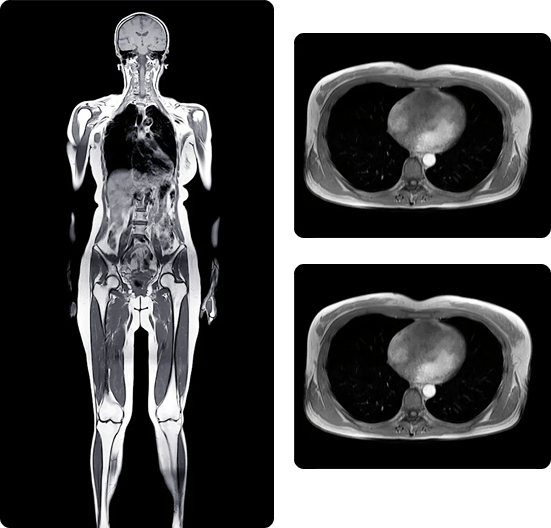

Whole-Body MRI — Now Available at Harding Radiology

Whole-Body MRI is a non-invasive screening that produces detailed images of the brain, spine, chest, abdomen, pelvis, major organ systems, and vasculature – without radiation or contrast agents. It is designed for patients who want a thorough internal health assessment, and for physicians seeking a broader diagnostic picture outside of symptom-specific referrals.

Comprehensive. Radiation-free. One session.

What Whole-Body MRI Can Reveal

Early-stage cancers and tumors

Neurological abnormalities

Cardiovascular and vascular changes

Organ health abnormalities

Spinal and musculoskeletal conditions

Inflammatory changes

Liver and kidney irregularities

Pancreatic and abdominal findings

Joint and cartilage degeneration

Hidden structural abnormalities

Chronic disease indicators

Preventive whole-body insights